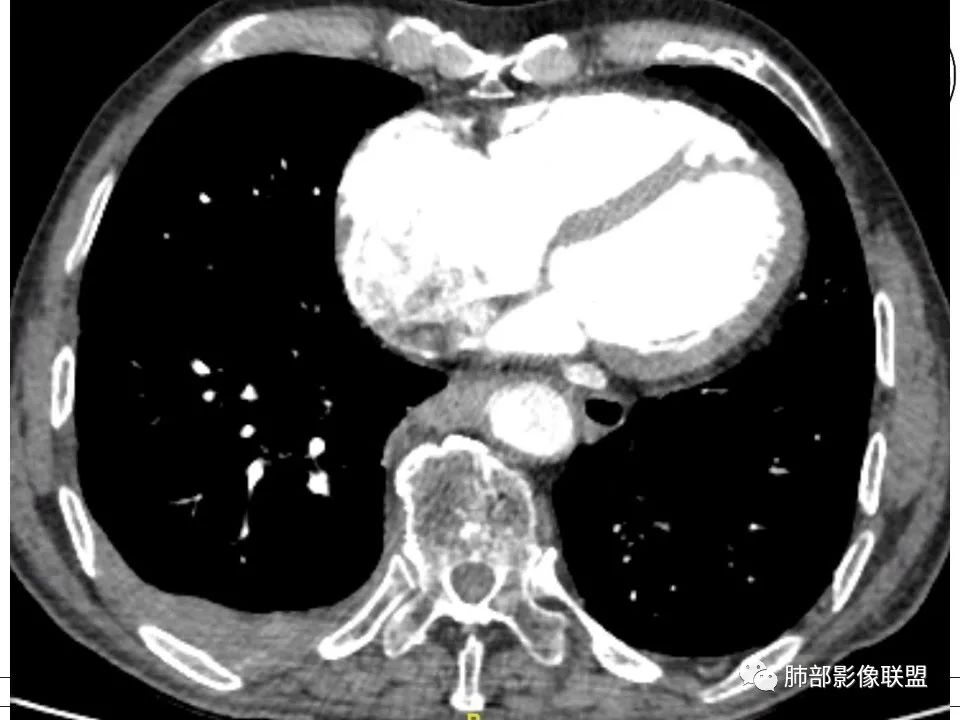

1、老年男性,右侧后胸壁软组织肿块延伸范围较广(至后纵隔主动脉旁),平扫密度均匀稍高,增强扫描均匀强化,其间走行肋间动脉包埋、漂浮(夹心三明治),部分包绕肋骨,肋骨骨质未见明显吸收破坏! 医学百科网 | YxBaike.Com

2、胸膜掀起或尾征,胸壁肋间肌及脂肪间隙浸润,肋间动脉供血。 医学百科网 | YxBaike.Com

3、纵隔淋巴结多发肿大,部分有融合。

4、双侧未见典型胸膜斑,提示石棉非长期接触。胸膜病变不广泛。淋巴结改变与胸膜病灶不相称。 医学百科网 | YxBaike.Com

5、良性胸膜间皮瘤局限、规则高密度。恶性间皮瘤胸膜呈波浪状,常伴胸水。 医学百科网 | YxBaike.Com

6、老年患者转移瘤多见。双侧多发,易伴胸水。胸壁侵犯肋骨破坏为主。常有原发肿瘤。